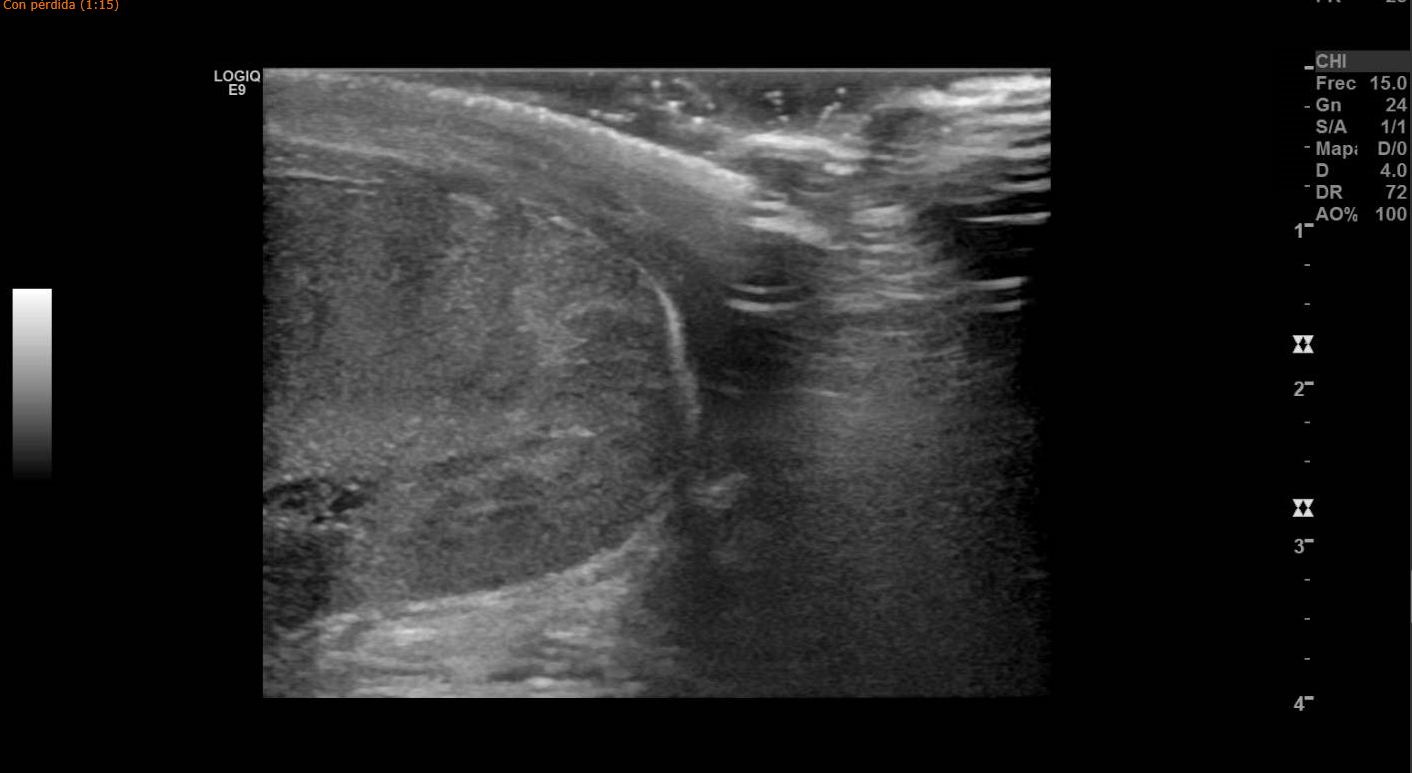

Para confirmar la sospecha se le realiza ecografía testicular, apreciando colección hemática en borde superior de bolsa escrotal izquierda, conservando flujo arterial y venoso. Impresiona de línea hipoecogénica que atraviesa el parénquima testicular, correspondiendo con rotura traumática de testículo izquierdo.